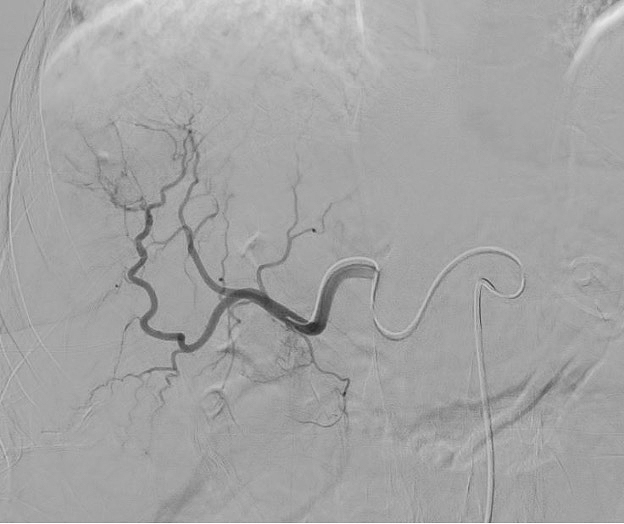

Equipped with sophisticated advanced image-guidance systems and multi-imaging modalities, our physicians may now better visualize and treat patients with complicated diseases. This system includes technology to make this easier in both 2D and 3D with dose reduction technology. It is equipped with integrated Intravascular Ultrasound. Vessel Navigation guidance, 2D Vessel Perfusion, 3D roadmap and Vessel quantitative measurements are offered as well. Vessel Navigator allows reuse of 3D vascular anatomical information from existing CTA and MRA datasets as a 3D roadmap overlay on live X-ray images. With its sophisticated visualization, it provides an intuitive and continuous 3D roadmap to guide you through vasculature during the entire procedure. The system is connected to our PACS system allowing us to visualize previous diagnostic images inside the room.

Stephan Wicky van Doyer, MD: “The performance, technology and quality of the new angio suite is absolutely fantastic. The room size allows multiple providers to feel comfortable and safe. It allows us to perform very challenging procedures in a safe and secure environment for the patient benefit. Different imaging guidance systems such as IVUS and Navigation, shorten the duration of the procedure and our patients also are exposed to a much lower radiation dose.”